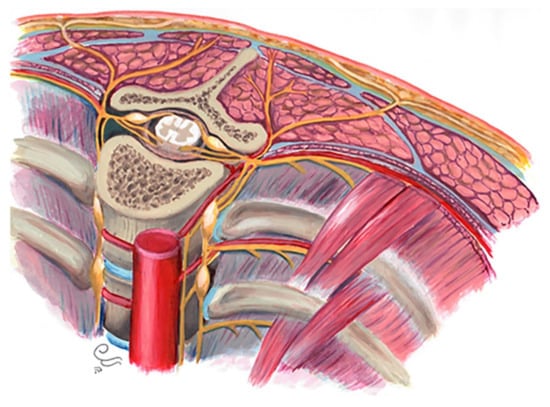

In this article, we focus on the posteromedial segment of the thoracic wall. The medial aspect of the posterior chest wall consists of multiple components detailed below (Figure 1):

Figure 1.

Posteromedial thorax anatomy, consisting of multiple components: skeletal components, muscles, nerves, ligaments, subcutaneous fat, fascia, skin, and vascular feeding tissues.

- Osseous/cartilaginous parts: 12 thoracic spine vertebrae, 12 ribs, and intervertebral discs.

- Muscles: Intercostal muscles (external, internal, and innermost), subcostalis, and transverse thoracic.

- Nerves: intercostal nerves, dorsal root ganglions, and sympathetic trunk.

- Vascular tissues: Intercostal vessels feed above components.

- Subcutaneous fat: beneath the superficial fascia and builds the padding for underlying muscles and bones.

- Superficial fascia and skin: acting as protecting layers [5,12].